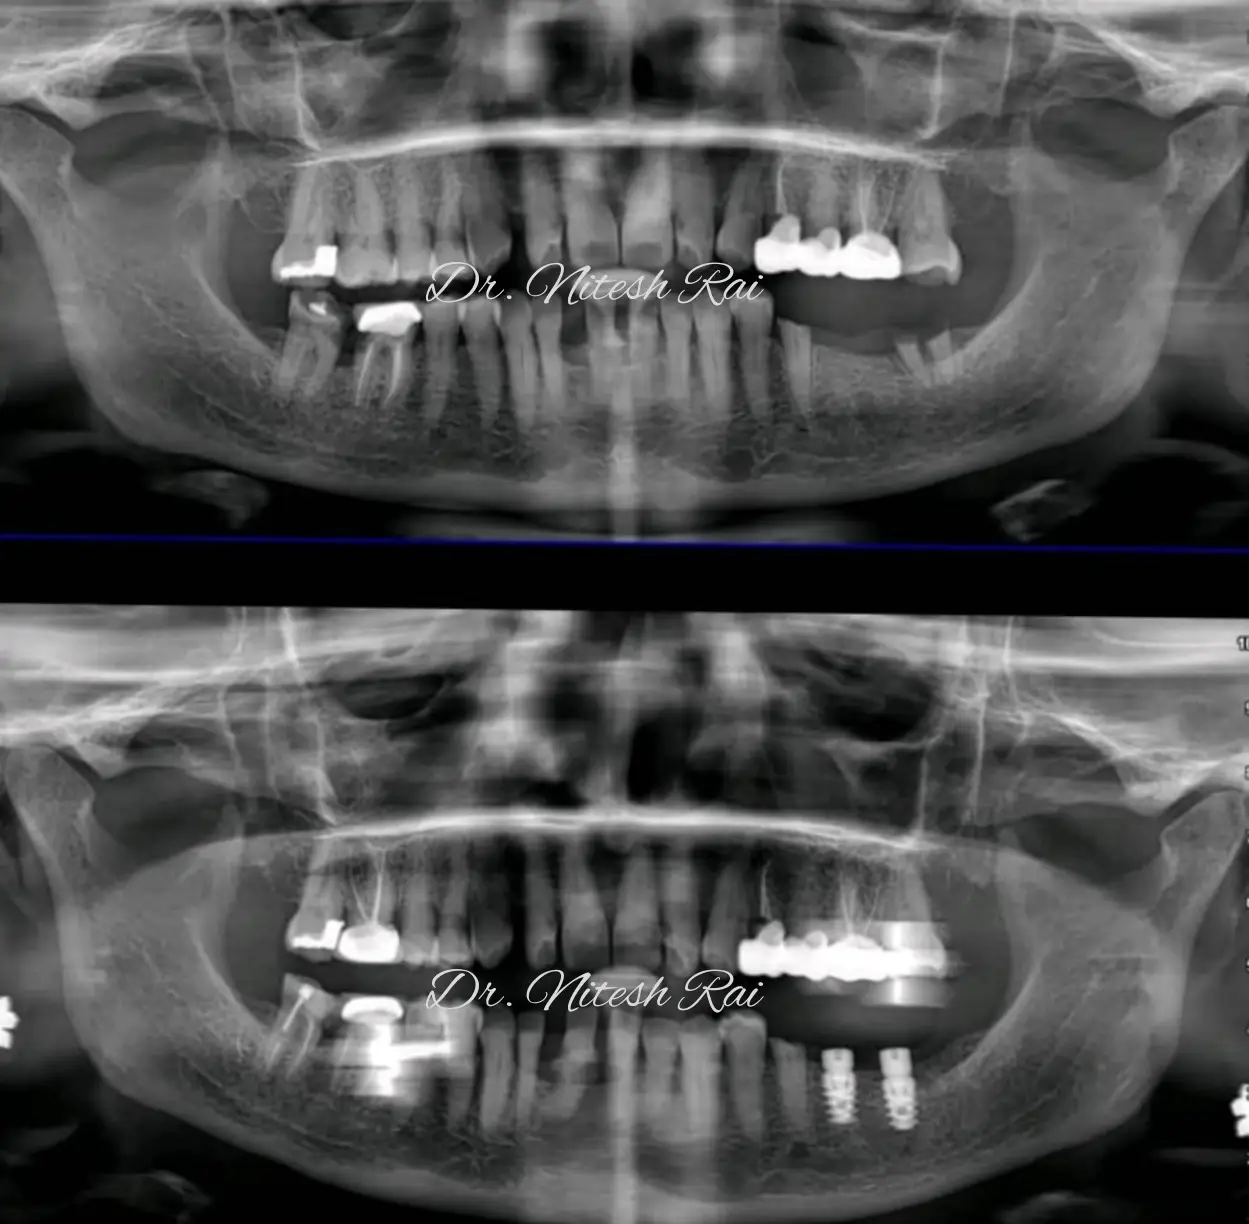

Dr Nitesh Rai, specializes in replacement of teeth with complete dentures, removable partial dentures, fixed partial dentures and Implants.

He has been actively involved in providing implant treatment for over two decades. He is also a committed academician, educating dental students and has been associated with Krishnadevaraya college of Dental sciences, Bengaluru as a Senior Professor, PG Guide and teacher in the Department of Prosthodontics, Crown and Bridge and Implant.